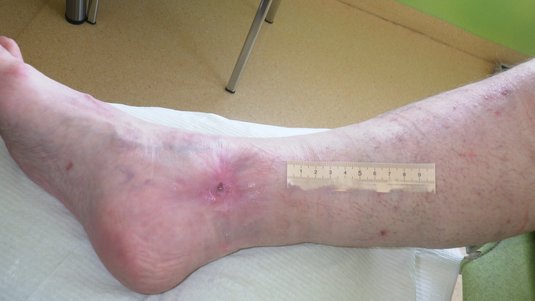

Blickdiagnostik CVI und Ulcus cruris venosum​

• ​Blickdiagnostik des Beins

• Wunddiagnostik bei venösen Ulcera

Blickdiagnostik pAVK und Ulcus cruris arteriosum

• Wunddiagnostik bei arteriellen Ulcera

Gegenüberstellung eines UCV und UCA

• Sicherung der Diagnose

• Typische Merkmale zusammengefasst

• Angepasste Wundversorgung